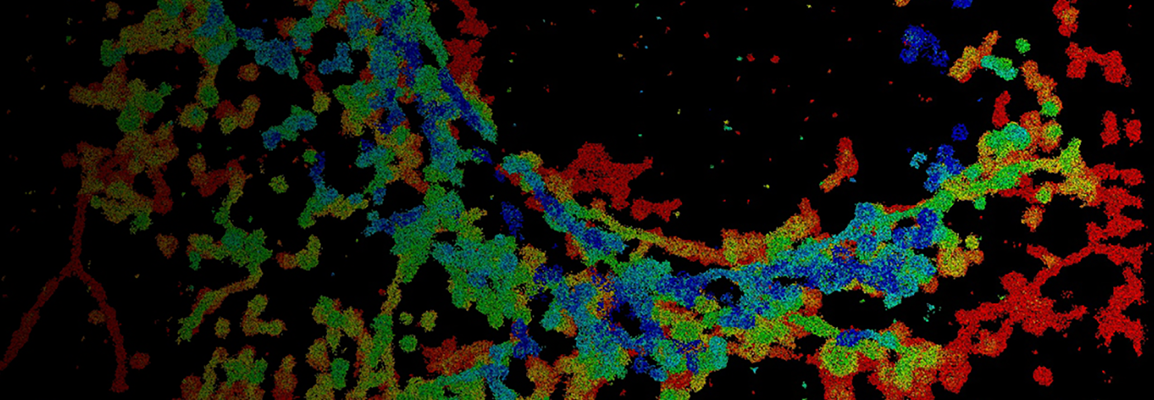

dSTORM Imaging of Neuronal GABAAR Spatial Patterning Regulated by GABA and Astrocytic Cholesterol

Understanding how membrane organization influences receptor function is a growing frontier in cellular neuroscience. In this talk, I will share how we used super-resolution direct stochastic optical reconstruction microscopy (dSTORM) imaging to uncover dynamic, lipid-dependent trafficking of γ-aminobutyric acid type A receptors (GABAARs) in primary cortical neurons. Upon GABA activation, GABAARs translocate from cholesterol-rich GM1 lipid rafts to PIP2-enriched domains, aligning temporally with receptor activation and desensitization. This translocation is disrupted by astrocytic cholesterol, resulting in receptor retention in rafts and enhanced endocytosis. Through advanced imaging, we resolved the nanoscopic movement of receptors between membrane domains and identified a cholesterol-sensitive mechanism contributing to synaptic dysfunction in neurodegeneration.